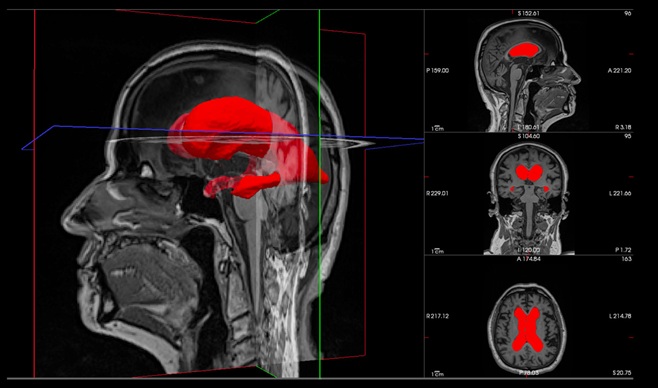

Interfaz cortical flexible de grafeno permite mapeo en tiempo real durante cirugía de tumores